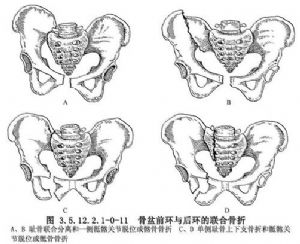

3.骨盆環的聯合骨折(Ⅲ型) 骨盆環有兩處完全斷裂而失去其穩定性,併發症發生率和病死率高。這種嚴重型骨盆骨折可再分爲兩種類型:①骨盆前環雙側恥骨上下支骨折;②骨盆前環與後環聯合骨折,骨盆分爲兩半而完全失去穩定性。常見的是恥骨聯合分離和一側骶髂關節脫位或髂骨、骶骨骨折,或者爲單側恥骨上下支骨折合併骶髂關節脫位或骶骨、髂骨骨折(圖3.5.12.2.1-0-11)。骨盆變形因外力作用不同而異。前後向擠壓力是造成骨盆外翻外旋和前部張開變形(分離型),側方擠壓將使傷側半個骨盆向中線移位和內翻內旋變形(壓縮型),沿身體縱軸外力則造成傷側骨盆向頭側移位(垂直剪切分離型)。骨盆前環恥骨段兩處斷裂適用外固定器治療,可使前環的分離或重疊獲得滿意的復位。對合並尿道、膀胱損傷或陰道、直腸傷的開放性骨折,術後用骨外固定便於觀察和處理傷口。前後環聯合骨折脫位,骨外固定前應先做股骨髁上大重量牽引,待半側骨盆環骨折脫位已復位,再安裝骨盆外固定器。如半側骨盆骨折脫位難以復位,則應切開復位,骶髂關節用2~3枚螺釘內固定,用骨盆外固定器加壓固定前環骨折或恥骨分離。單純用骨盆外固定器固定沒有可靠的穩定力,必須配合下肢骨牽引或結合手術治療(圖3.5.12.2.1-0-12)。骨盆骨折的影像表現見(圖3.5.12.2.1-0-13~3.5.12.2.1-0-14)